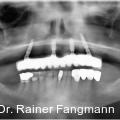

Die Daten der DMS V zeigen, dass in der Patientenaltersgruppe der 65- bis 74-Jährigen im Durchschnitt 12,5 Prozent völlig zahnlos sind. Die zahnlosen Ober- und Unterkiefer stellen eine typische Indikation für herausnehmbaren Zahnersatz dar. Fotos: © Dr. Dr. Rainer Fangmann